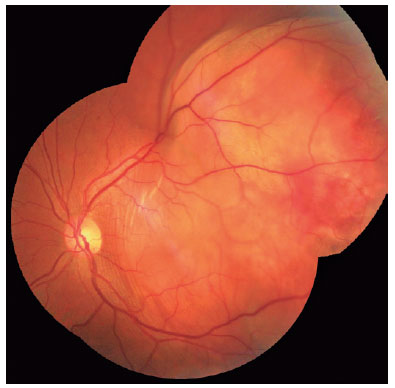

The ophthalmologic evaluation revealed a best-corrected visual acuity of 20/20 in the right eye (oculus dextrus [OD]) and counting fingers at 1.5 m in the left eye (OS). No changes were found on the biomicroscopy of the anterior segment in either eye (oculus uterque [OU]), including no anterior chamber or vitreous reaction. The intraocular pressure was 12 mmHg in OU. Fundoscopy revealed no abnormalities in the OD but revealed a large yellowish choroidal lesion in the temporal region of the posterior pole of the OS, with mild subretinal hemorrhage, associated with serous detachment of the perilesional retina (Figure 1A). US of the OS confirmed the presence of a choroidal mass temporally to the fovea, with medium and homogenous internal echogenicity, associated with serous retinal detachment (Figure 1B).